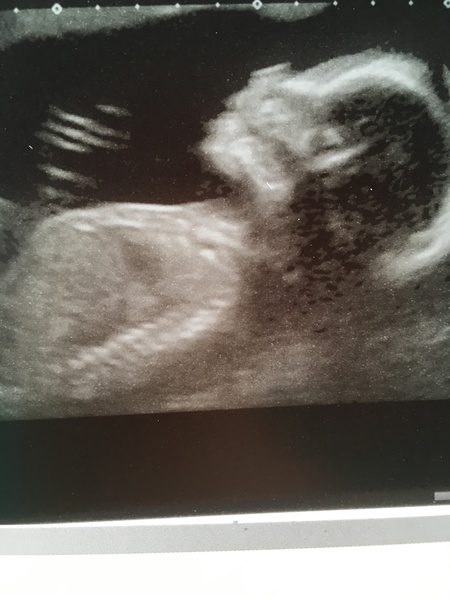

Please allow me a moment of indulgence everyone with the attached picture... everything looks good, anterior placenta so good reason for feeling no movements. I wasn't even sick on the sonographer. Today is a good day. Grin

fourcorneredcircle What a nice photo. It must be alarming not to feel movements; so glad that you got confiirmation as to why.

FOUr. A lovely scan pic and extra bonus not being sick on scan lady

Four What a lovely scan!!!! Kayleigh I'm sorry that you're having such a bad time, the ladies here are the best at wonderful advice and support so you're in the right place. Hugs.

Thanks for the nice comments about scan. We are team surprise but I think I saw meat and two veg... in my head up until that moment I was sure it was a girl (probably based on old wives tales about vomit!). Now I am unsure.